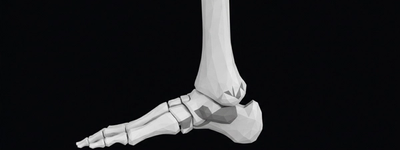

X-Ray of the Foot: Common Uses, Conditions Diagnosed, and What to Expect

2/11/2026